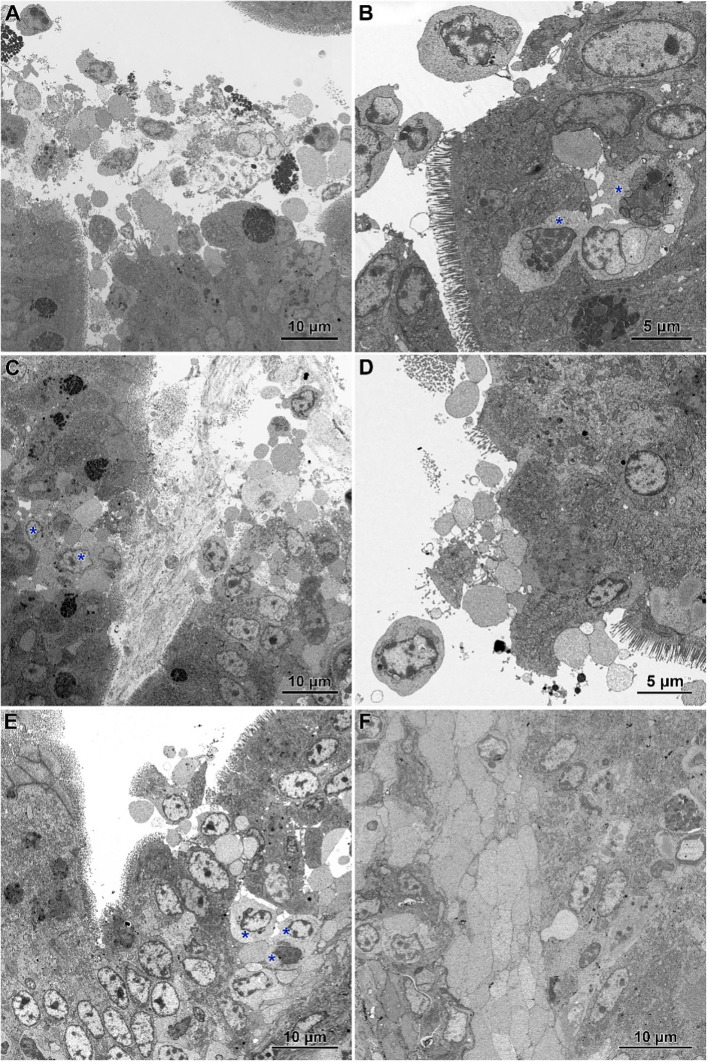

Electron microscopy revealed the presence of small necrotic regions within the epithelium covering both the apical and lateral surfaces of the intestinal villi in chickens infected with C. perfringens (f6). In addition to necrotic cells and cellular debris, these regions comprised abnormal enterocytes lacking cell polarity and microvilli. The cell debris was also present in the intestine lumen over the necrotic regions. The apical portions of villi, described at light microscopy level as devoid of the epithelium cover, contained necrotic cells, cellular debris, and numerous inflammatory cells, but also irregularly shaped enterocytes without microvilli (f6). Enterocytes in these areas were loosely attached and did not form the tight junctions. Ultrastructural analysis also revealed areas where enterocytes formed a continuous or nearly continuous layer but were highly irregular in shape and devoid of microvilli (f6). The stroma of some villi contained numerous inflammatory cells, frequently with foamy cytoplasm (f6) and an increased presence of smooth muscle cells (f6).

Infected chickens treated with CBD, CBD + nano-Se, or nano-Se displayed similar ultrastructural changes as those infected with C. perfringens but not supplemented with these compounds (f7). Necrotic foci covered with cellular debris (f7), areas of abnormal epithelium containing irregularly shaped enterocytes without microvilli (f7), intense infiltration of the epithelium by lymphocytes (f7), and the presence of inflammatory cells with foamy cytoplasm in the villi stroma (f7) were common across all infected groups receiving CBD, nano-Se, or CBD + nano-Se.